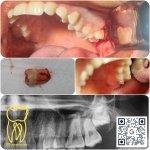

جراحی دندان نهفته

کشیدن دندان

جراحی افزایش طول تاج